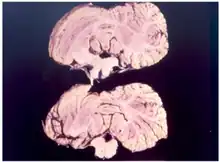

La maladie provoquée par l'accumulation de la protéine prion, ramollit les tissus du cerveau jusqu'à le rendre spongieux.